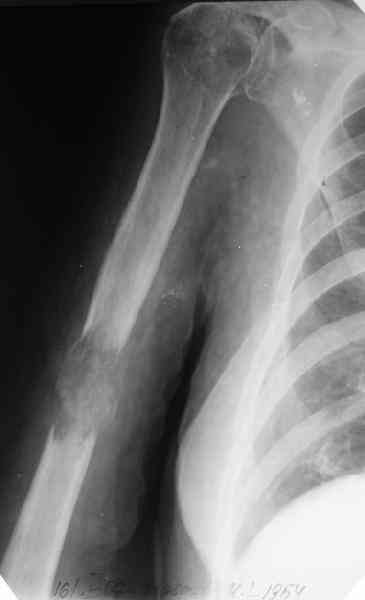

Женщина 53 лет получила патологический перелом правого плеча в феварле, и левого в марте - mts из невыясненного первичного очага.

Онкологи провели облучение, руки на косынки, время от времени наблюдают, вводили зомету.На нас вышли родственники. Состояние пациентки уже не очень, анемия (Hb -50-60 г/л), исхудалв, но асцита нет, в легких чисто. Поскольку женщина совершенно беспомощна, решили сделать остеосиннтез.

Сегодня сделали, Fixion диаметром 7,4 мм. Обе пперации продолжались по 7 мин. Картинки в приложении. Наркоз был диприваном, на спонтанном дыхании. По крайней мере, пока довольны хотя бы анестезиологи, похоже, не верили, что управимся меньше, чем за час ;-)

Гвоздик 7,4 расширяется до 11 мм. Не маловато ли, судя по снимкам?

Обсалютным показанием для использования этого стержня,из моей практики, являетются поперечные переломы диафиза пдечевой и большеберцовой костей.Преимущество его в удобстве репозиции и продалжительности операчии.Недостаток в сдабой ротационной стабильности.Учитывая состояние больной,метод был выбран правильно.Мы этих больных оперируем тогда когда приблизительный срок выживания превышает шесть месяцев и конечно же всотрудничестве с окологами.

7,4 мм, рсширяющийся до 11 мм, в принципе, достаточно для плеча. Хотя мне тоже показалось, что можно было бы и потолще. Вообще есть и следующий диаметр, 8,5 мм, расширяющийся до 13,5 мм, но его в наличии на сегодня не было.